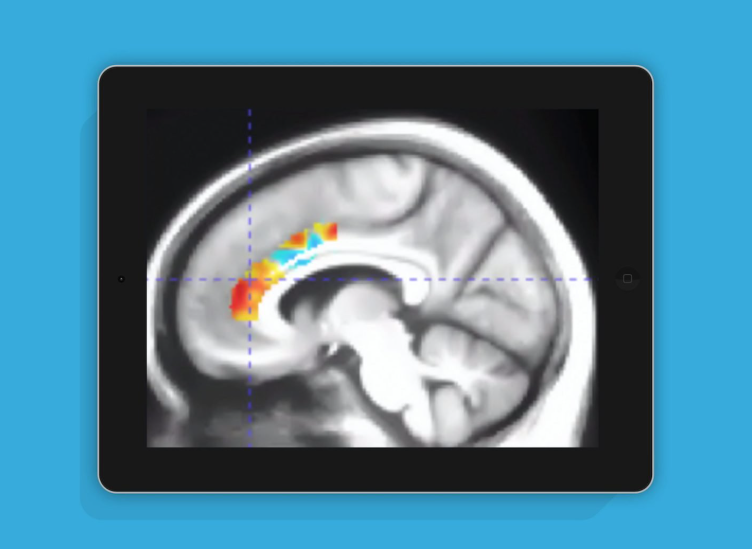

·来自美国的Posit Science Corporation公司的Mouna Attarha领导的研究团队日前发表题为《Effects of Computerized Cognitive Training on Vesicular Acetylcholine Transporter Levels using [18F]Fluoroethoxybenzovesamicol Positron Emission Tomography in Healthy Older Adults: Results from the Improving Neurological Health in Aging via Neuroplasticity-based Computerized Exercise (INHANCE) Randomized Clinical Trial([18F]》的研究论文,系统分析了玩大脑训练类游戏与脑退化之间的联系。

·研究团队招募了92名高龄实验者,平均年龄71.9岁,平均受教育时长16.5年,开启数个月的实际测试,结果很令人惊喜,玩家游玩10周大脑训练类游戏的效果就可以抵消10年脑退化程度。